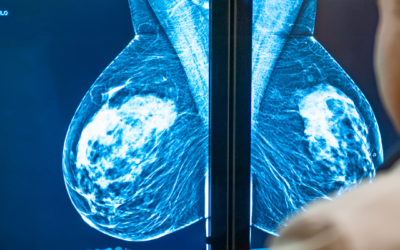

Mamografías

Mamografía diagnóstica y de tamizaje para la detección temprana del cáncer de mama, con equipos modernos y radiólogos expertos.